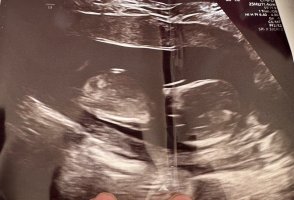

Her er det ikke noen kjønnsorgan som er synlig dessverre :/Er det tissen hans/hennes vi ser her? Jentetiss eller guttetiss, tror dere??

Ikke her heller sikkert? Mente kanskje det under beina kanskje kunne være kjønnsorganet, men er sikker noe annet ja..Her er det ikke noen kjønnsorgan som er synlig dessverre :/

Den der er vanskeligEr det tissen hans/hennes vi ser her? Jentetiss eller guttetiss, tror dere??

Ikke noe som peker åpenbart opp hvertfall, uten at jeg har peiling. Så vi sier jente, hehe Det er det jeg tror selv ogsåDen der er vanskelig

Ikke noe som peker åpenbart opp hvertfall, uten at jeg har peiling. Så vi sier jente, hehe